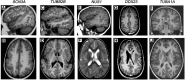

Bilateral perisylvian polymicrogyria is the most common form of regional polymicrogyria within malformations of cortical development, constituting 20% of all malformations of cortical development. Bilateral perisylvian polymicrogyria is characterized by an excessive folding of the cerebral cortex and abnormal cortical layering. Notable clinical features include upper motoneuron dysfunction, dysarthria and asymmetric quadriparesis. Cognitive impairment and epilepsy are frequently observed. To identify genetic variants underlying bilateral perisylvian polymicrogyria in Finland, we examined 21 families using standard exome sequencing, complemented by optical genome mapping and/or deep exome sequencing. Pathogenic or likely pathogenic variants were identified in 5/21 (24%) of families, of which all were confirmed as de novo. These variants were identified in five genes, i.e. DDX23, NUS1, SCN3A, TUBA1A and TUBB2B, with NUS1 and DDX23 being associated with bilateral perisylvian polymicrogyria for the first time. In conclusion, our results confirm the previously reported genetic heterogeneity of bilateral perisylvian polymicrogyria and underscore the necessity of more advanced methods to elucidate the genetic background of bilateral perisylvian polymicrogyria.